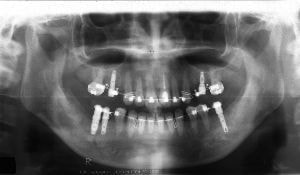

最近は、人工歯の適応症の拡大により天然歯+人工歯(インプラント補綴)にり、本来あるべき歯並びが再現できるようになり、高齢者の患者層が増えてきています。

治療例2 (補綴処置+矯正)